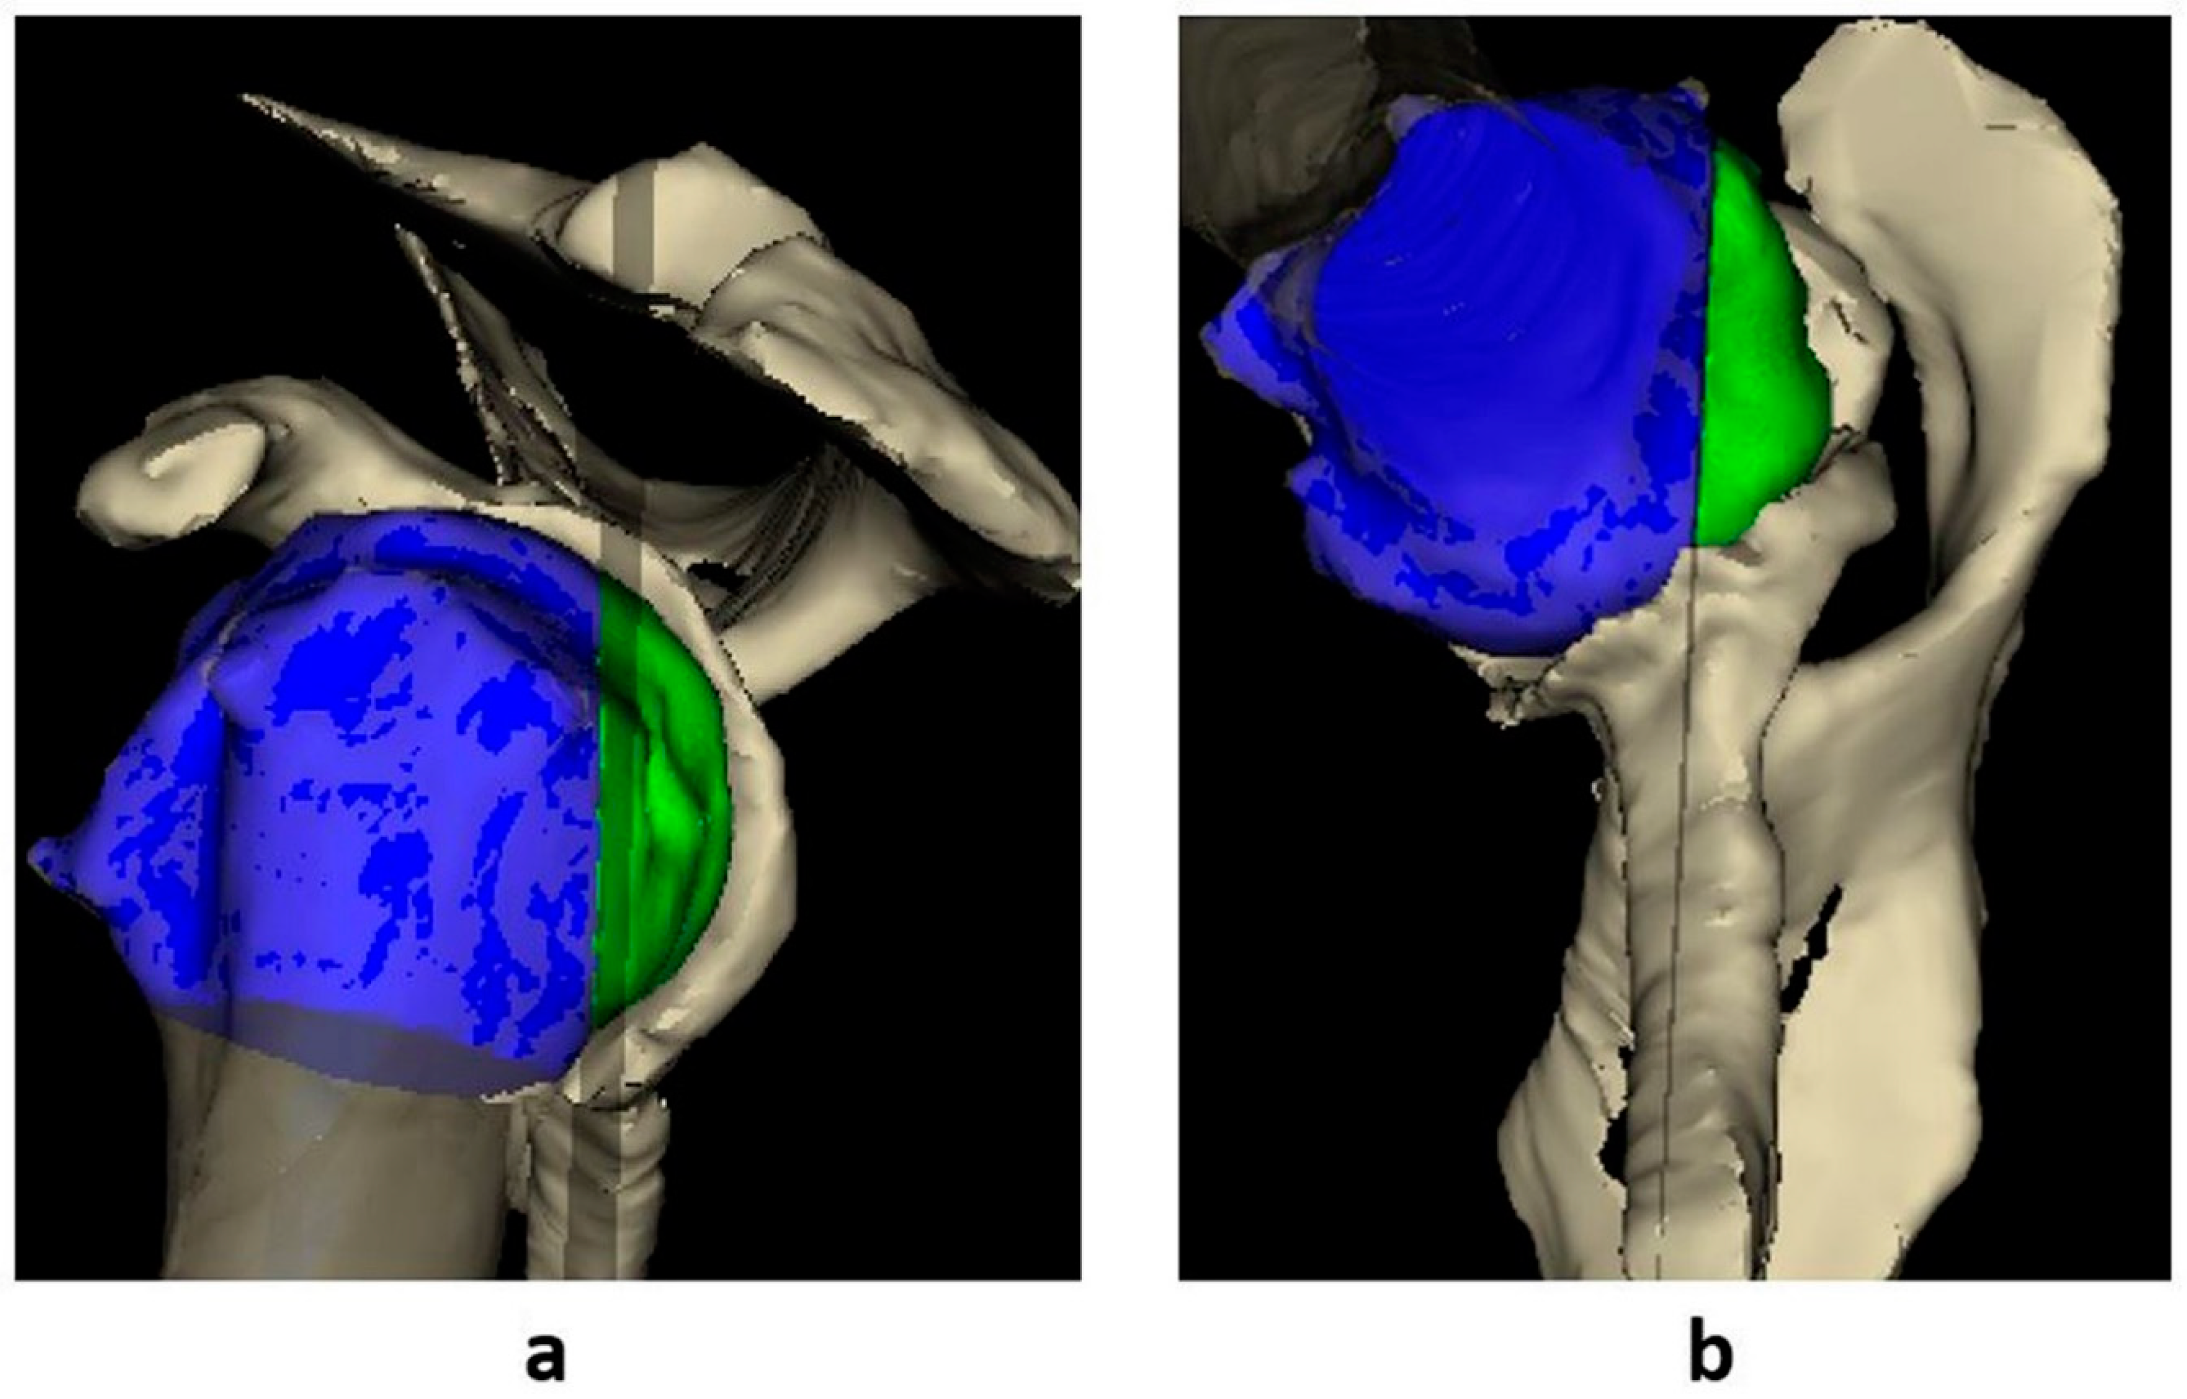

2.2. Imaging Analysis